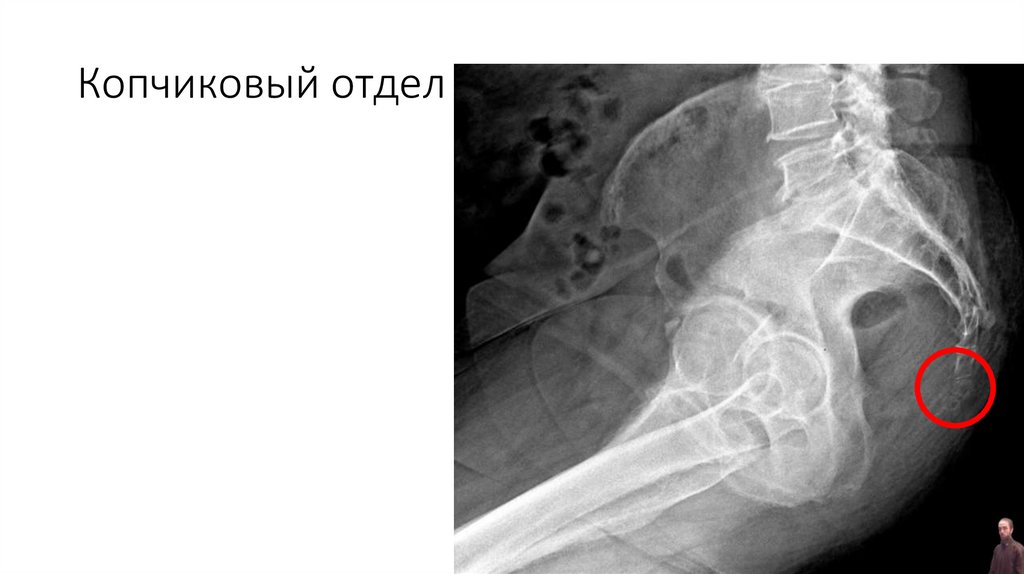

Копчиковый отдел